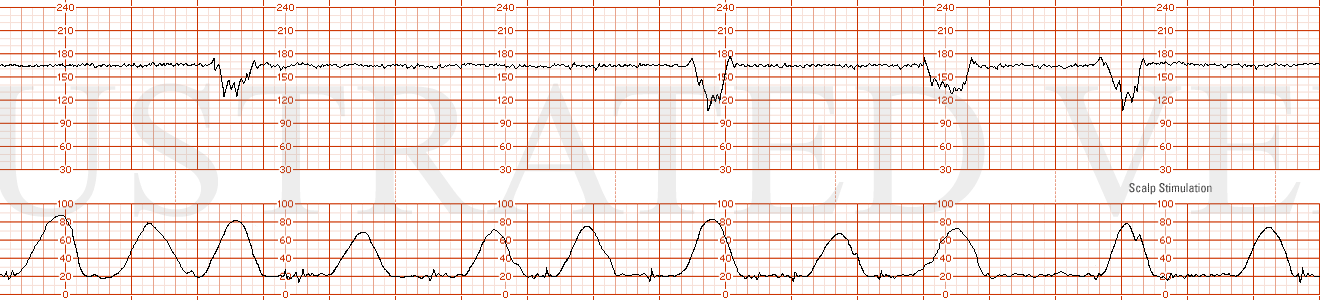

STRIP 73

1. 1st and 2nd panel:

Contractions: 7-8 60-70 second contractions in 20 min. See exception below re deceleration associated contractions – 3 run together concluding 30 sec or so before end of deceleration. (2nd too long, last 2 also to long)

Baseline 140 bpm for first 5 minutes w 7-8 bpm variability (move decel over to left to the 5th min, adjust contraction tripling)

Decelerations deceleration x 5.5 minutes to initial nadir of 110 bpm x 45 seconds, followed by gradual return to 140 bpm. The deceleration parallels a triple contraction with total duration of 5 minutes – first contraction relative magnitude 1; second .75 and third .5 magnitude of first.

Variability moderate at 145 pm after deceleration

Accelerations1 no accelerations after deceleration (move accel over to min 1)

3rd panel:

Contractions: 7-8 60-70 second contractions in 20 min. Contractions at more predictable intervals with no coupling or tripling of contractions (1st 3rd by 30-40secs, 5th by 20secs, 7th 40secs shorter)

Baseline 145 bpm for first 5 minutes

Decelerations One deceleration x 6 minutes to initial nadir of 115 bpm x 35 seconds, followed by gradual return to 150 bpm baseline (move decel over to min 5)

Variability minimum- moderate at 4-5 bpm at 145 bpm baseline rate after deceleration

Accelerations2 no accelerations after deceleration